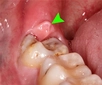

Diş ekimi, günümüzde oldukça yaygın bir işlem olmasına rağmen, her cerrahi müdahalede olduğu gibi bazı riskleri de beraberinde getirebilir. Enfeksiyon ve vücut reddi, bu işlemin potansiyel komplikasyonları arasında yer alır. Ancak, bu riskler uygun önlemlerle önemli ölçüde azaltılabilir.

Riskleri Minimize Etme Yöntemleri

1. Uzman Seçimi: Diş ekimi yapacak olan doktorun deneyimi ve uzmanlığı, işlemin güvenliği açısından kritik öneme sahiptir. Güvenilir bir hekim seçmek, komplikasyon riskini azaltır.

2. Steril Ortam: İşlem sırasında kullanılan aletlerin ve ortamın steril olmasına dikkat edilmelidir.

3. Hastanın Genel Sağlık Durumu: İşlem öncesi genel sağlık kontrolü yapmak, mevcut sağlık sorunlarının tespit edilmesine ve buna göre önlem alınmasına yardımcı olur.

4. İlaç Kullanımı: Doktorun önerdiği antibiyotik ve ağrı kesicilerin düzenli kullanımı enfeksiyon riskini azaltabilir.